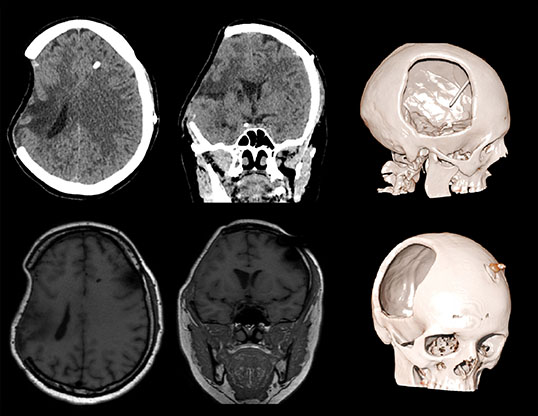

Симптом тонущего лоскута (парадоксальная церебральная грыжа) – является редким и потенциально смертельным осложнением после массивной декомпрессивной краниотомии, проявляющееся в виде инвагинации кожного лоскута в направлении, противоположном участку краниотомии. Триггерным механизмом данного состояния является резкое превышение атмосферного давления над внутричерепным, спонтанно или спровоцированное люмбальной пункцией или гипердренажём цереброспинальной жидкости (после шунтирующих операций, обезвоживания, смена позиции головы).   Данное состояние подлежит неотложной нейрохирургической помощи.

Пациент А., перенесший тяжелую черепно-мозговую травму в ДТП. Состояние после правосторонней гемикраниотомии, эвакуации крупной субдуральной гематомы. Произведена ликворошунтирующая операция с установкой программируемого клапана давления . Через месяц пациент стал предъявлять прогрессирующие неврологические расстройства.

Визуализируется обширная инвагинация кожного лоскута в полость дефекта, смещение срединных структур влево, сдавление САП правого полушария и сглаженность борозд. Причиной данного состояния явилась гиперфункция шунта.

Данному пациенту была произведена краниопластика дефекта черепа, коррекция программируемого клапана давления. Пациент выписан на третьи сутки в удовлетворительном состоянии с полным регрессом неврологической симптоматики.